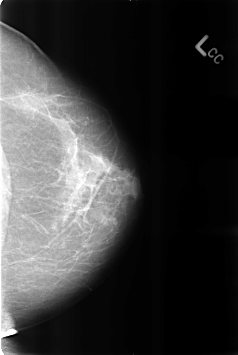

B_3207_1.LEFT_CC

LEFT_CC LINES 4608 PIXELS_PER_LINE 3088 BITS_PER_PIXEL 12 RESOLUTION 50 NON_OVERLAY